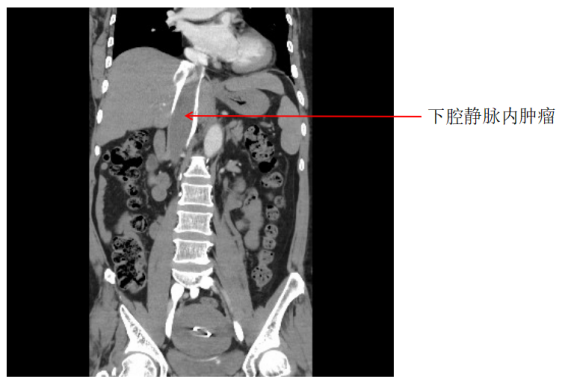

增强CT显示肿瘤沿着下腔静脉一直生长至右心房

北京清华长庚医院9月17日电曹战江 韩冬野)下腔静脉是人体内最大的静脉干,它收集下肢、盆腔和腹腔的静脉血,回流到右心房。而你能想象肿瘤就沿着这条线路,从子宫一直爬到了右心房吗?近日,北京清华长庚医院在执行院长董家鸿院士的带领下,汇集11个科室的力量,鼎力支持4科室医师接力上台,成功诊治了一例跨越人体半身的静脉内肿瘤患者。

经过初步的诊断,谢女士系“静脉内平滑肌瘤病”。这种肿瘤尽管在组织病理学上为良性病变,但其生长方式类似恶性肿瘤。该肿瘤原发于子宫或子宫外盆腔的静脉壁,顺静脉生长,最终可达心脏。一旦肿瘤脱落,可造成严重的循环障碍,具有潜在的猝死风险。手术切除原发肿瘤、腔静脉及右内肿瘤是最佳的治疗方法。